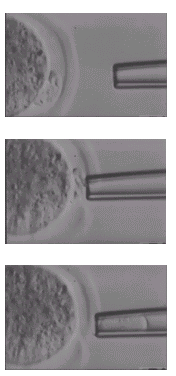

因此為了要幫助這些胚胎孵化,在顯微鏡下,適度的打薄透明帶或甚至在透明帶上鑿個洞讓胚胎流出來便成為許多實驗室一種想研發的新方法我們稱之為人工助孵(如圖二)。過去有人曾嘗試以化學方法如用強酸來腐蝕透明帶,或是機械方法如用細針來挑破透明帶以達到助孵的目地。但以化學方法助孵,需考慮化學藥品潛在對胚胎的毒性,以機械方法助孵不但技術困難,也增加胚胎暴露於外在環境的時間,因此成效並不顯著。

利用鐳射來作胚胎透明帶顯微切割則是目前最新與最有效的方法(如圖三)。鐳射具有精確,操作容易與不易傷害胚胎的特性(如圖四)。國外已有多篇研究報告證實其臨床的效果,此次首次引進國內,相信必會對所有不孕症患者帶來更多懷孕的機會。